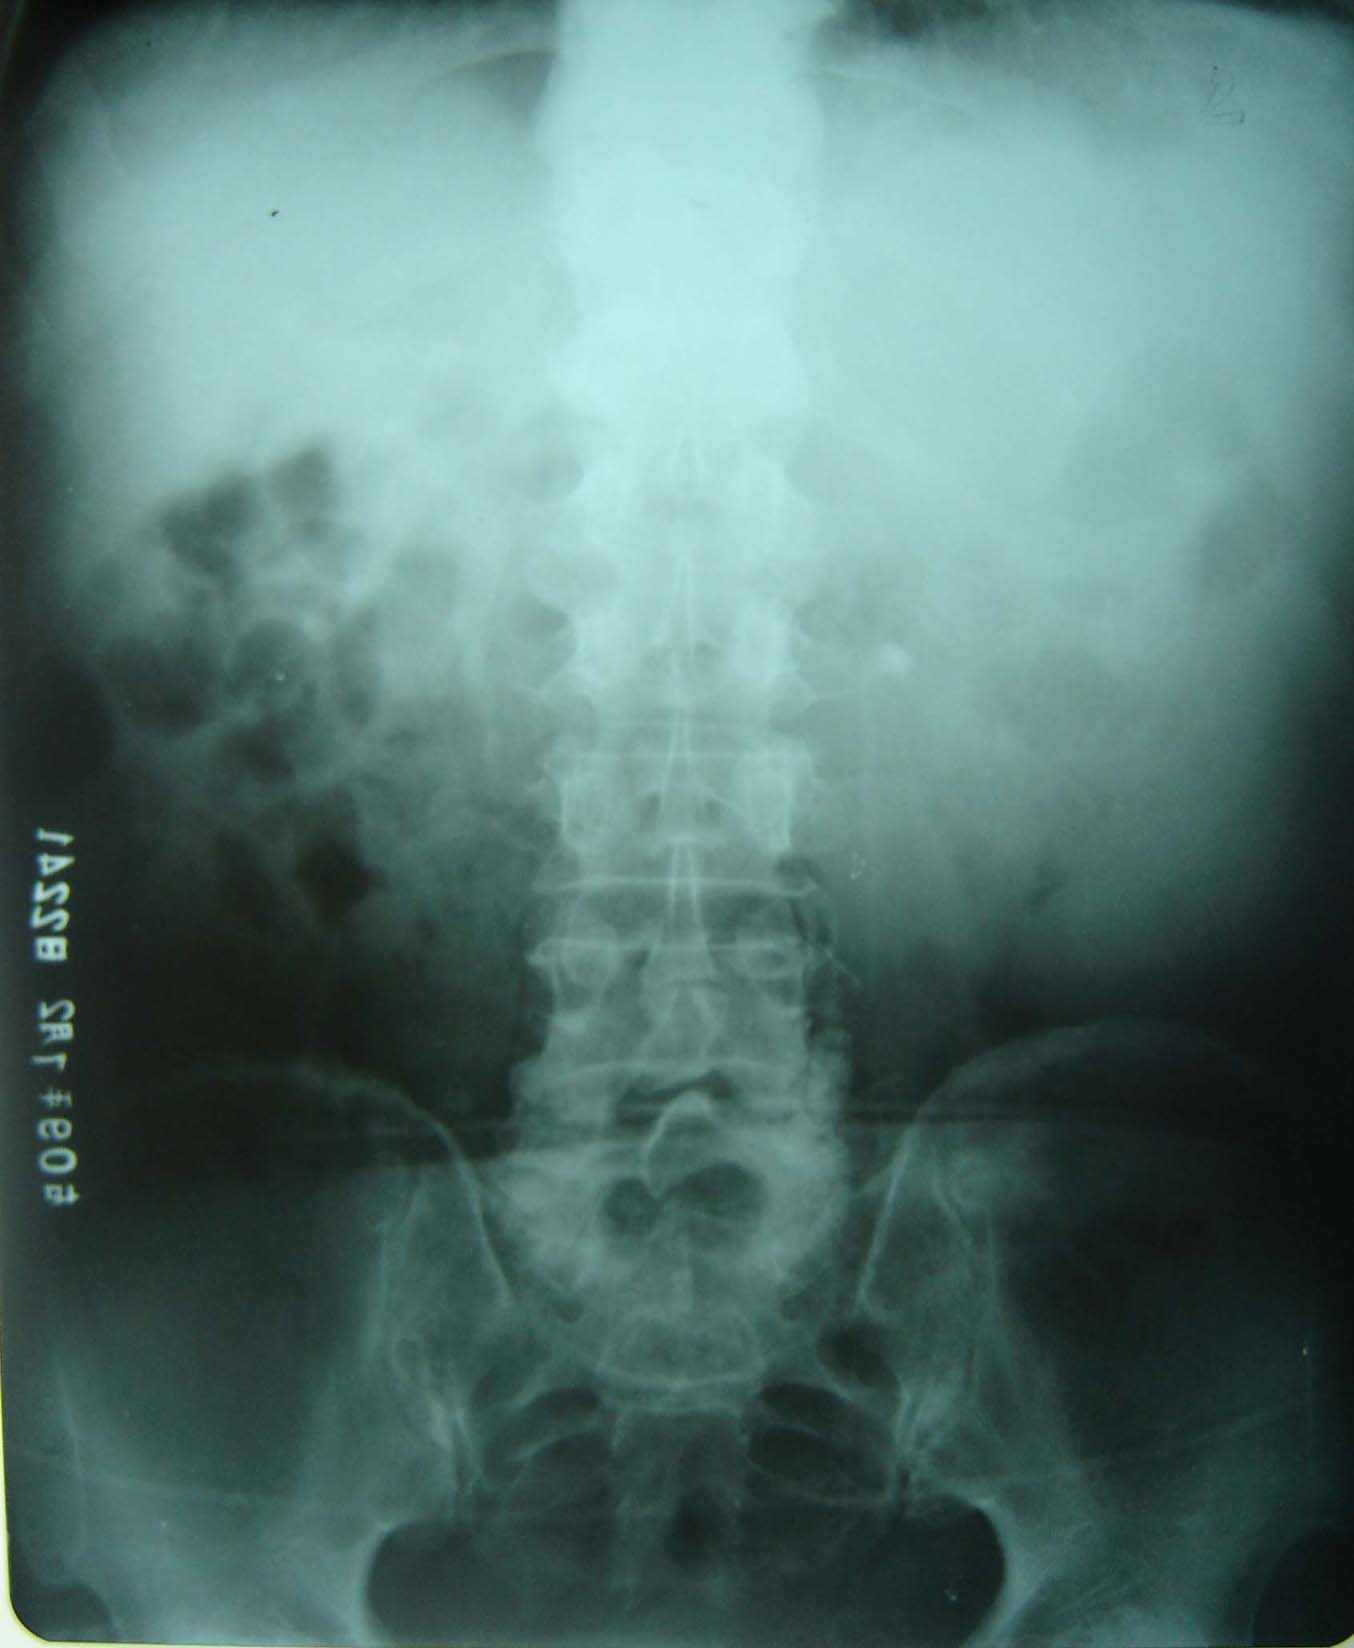

男、75岁、左季肋部疼痛,无其它不适。

建议把片子拍好一点,胸片两边漏了一半,kub又没包全,左肾区感觉有个小结石。

左侧少量胸腔积液?左侧输尿管上段结石?片子较模糊,l5si左侧水平好像有条形高密度影。

左侧胸腔积液,左侧输尿管上段结石。

1)左侧胸腔积液?2)左侧输尿管上段结石可能;建议行进一步检查。

左侧少量胸腔积液,左侧输尿管上段结石?

这是静脉肾盂造影的片子,输尿管显影,左侧高密度影不在输尿管显影区